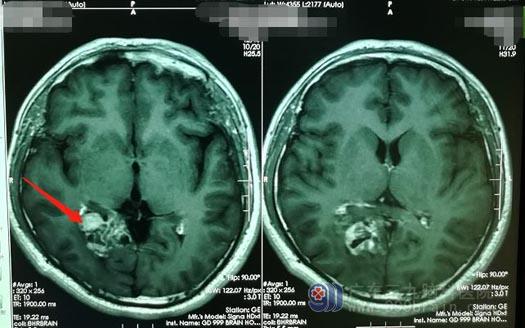

我院头颅MRI显示患者右侧颞顶枕叶-胼胝体压部存在占位病灶,结合患者临床症状,我院副院长、神经外五科主任鲁明认为患者颅内病变属于肿瘤性病变,初步怀疑是胶质瘤。由于肿瘤体积较大,已经明显压迫周围神经,鲁明建议尽快进行手术。

▲术前MR检查